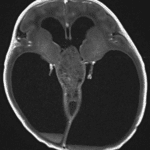

- Extensive corresponding mass effect on the midbrain with effacement of the cerebral aqueduct and associated severe obstructive hydrocephalus with cerebral parenchymal thinning

- Small volume hemorrhage layering in both lateral ventricles and fourth ventricle with rounded clot in the third ventricle

- Additional noncontiguous masses in the left cerebellopontine angle cistern and along the ependymal margin of the frontal horn of the left lateral ventricle at the caudothalamic groove